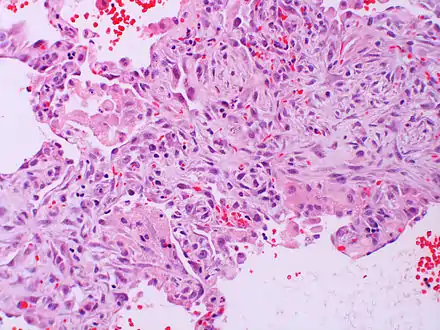

| Micrograph of diffuse alveolar damage, the histologic correlate of acute interstitial pneumonitis. H&E stain. | |

Rapid progression from initial symptoms to respiratory failure is a key feature. An X-ray that shows ARDS is necessary for diagnosis (fluid in the small air sacs (alveoli) in both lungs). In addition, a biopsy of the lung that shows organizing diffuse alveolar damage is required for diagnosis. This type of alveolar damage can be attributed to nonconcentrated and nonlocalized alveoli damage, marked alveolar septal edema with inflammatory cell infiltration, fibroblast proliferation, occasional hyaline membranes, and thickening of the alveolar walls. The septa are lined with atypical, hyperplastic type II pneumocytes, thus leading to the collapse of airspaces. Other diagnostic tests are useful in excluding other similar conditions, but history, X-ray, and biopsy are essential. These other tests may include basic blood work, blood cultures, and bronchoalveolar lavage. The clinical picture is similar to ARDS, but AIP differs from ARDS in that the cause for AIP is not known.

Acute interstitial pneumonia (AIP)/Idiopathic DAD